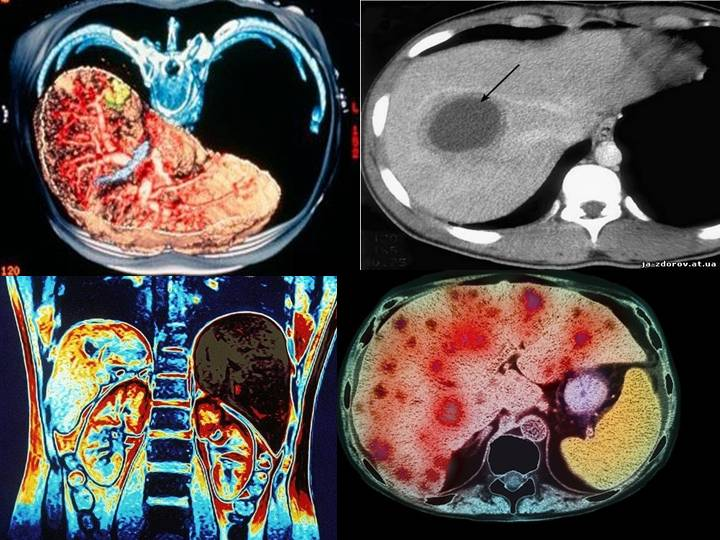

Виды роста злокачественных опухолей. Рост злокачественных новообразований. Злокачественные опухоли характеризуются. Форма злокачественной опухоли. ПЭТ кт онкология глиома. Метастазы в печени на ПЭТ кт.

ПЭТ кт онкология глиома. Метастазы в печени на ПЭТ кт. Лимфангиома брыжейки кт. Лимфома брыжейки тонкой кишки кт.

Глиома внутримозговая кт. Метастатические опухоли мозга. ПЭТ кт томограмма. Кт, ПЭТ И ПЭТ/кт. ПЭТ кт с контрастом. Скопление контраста ПЭТ кт.

ПЭТ кт томограмма. Кт, ПЭТ И ПЭТ/кт. ПЭТ кт с контрастом. Скопление контраста ПЭТ кт. Метастатическое поражение печени. Метастатические опухоли печени. Злокачественные образования печени.